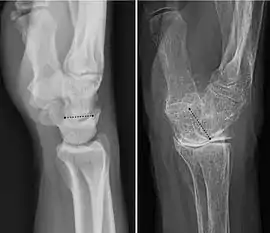

A wrist fracture usually means a fracture of the distal radius.